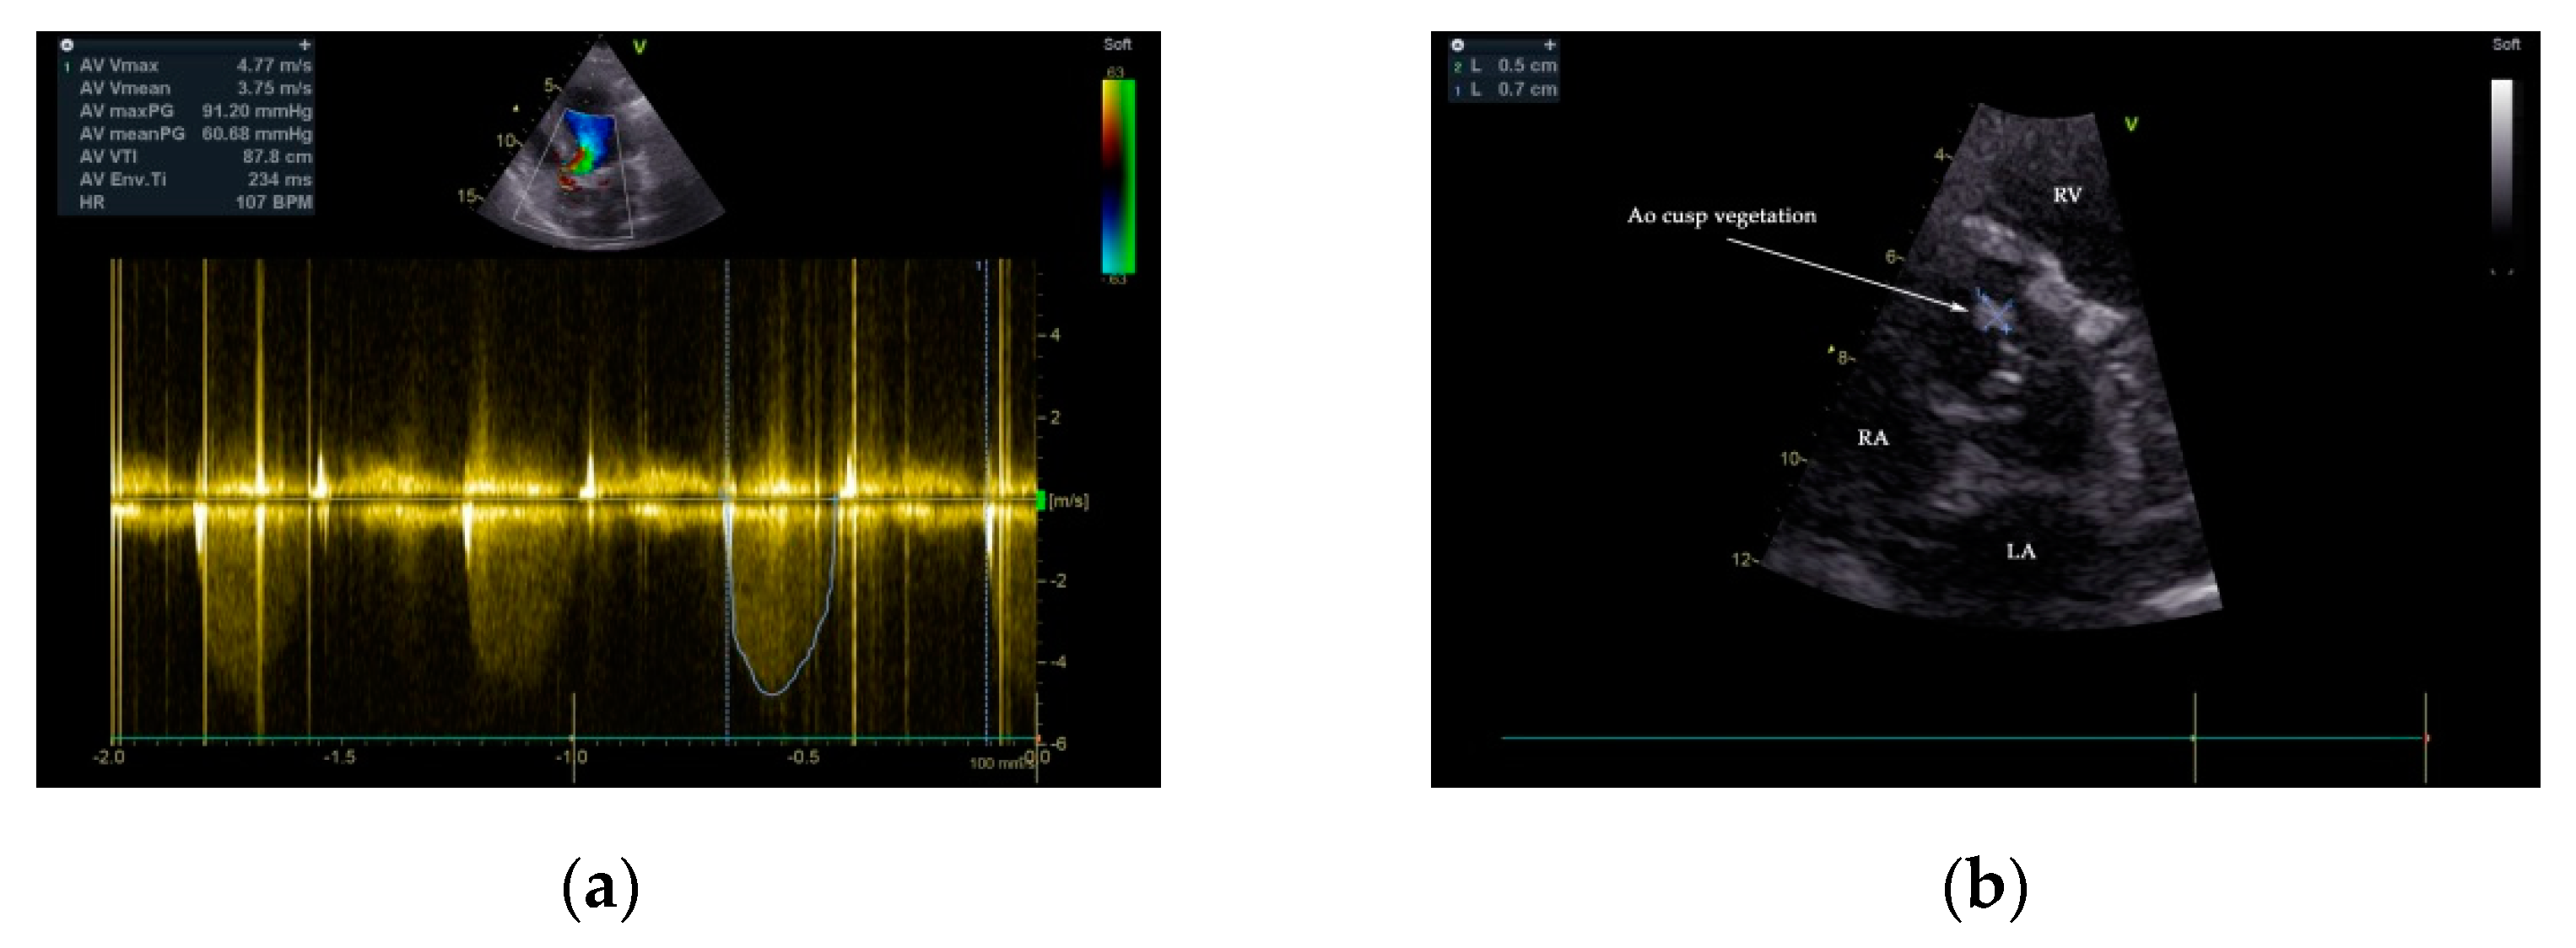

Two-dimensional transthoracic and transesophageal echocardiography (TTE and TOE, respectively) were performed (GE VividTM E9 ultrasound system, GE Healthcare, Boston, MA, USA). Analysis of TTE images denoted a large P-MAIVF (60 mm × 6 mm), LVH, normal dimensions of the left ventricle with an LV ejection fraction of 65% (modified Simpson’s biplane method), bicuspid aortic valve, and severe aortic stenosis (peak velocity: 4.8 m/s, gradient of 91/60 mm Hg, AVA: 0.51 cm2/m2). Mild aortic and mitral regurgitation were noted. A 5 mm × 7 mm vegetation was identified at the level on the anterior aortic cusp (Figure 2 and Figure 3). Echocardiographic assessment did not confirm pericardial effusion or the presence of pulmonary hypertension (Supplementary Movie S1).

Figure 3.

TTE 2D color flow and continuous Doppler 2D examination demonstrated severe aortic stenosis—aortic valve gradient 91/60 mmHg (a). The presence of a vegetation of 5 mm × 7 mm attached to the anterior cusp of the aortic valve is depicted (b).